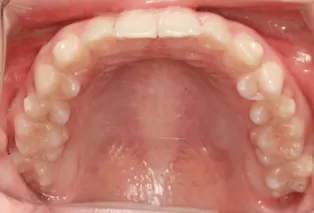

Intraoral photos